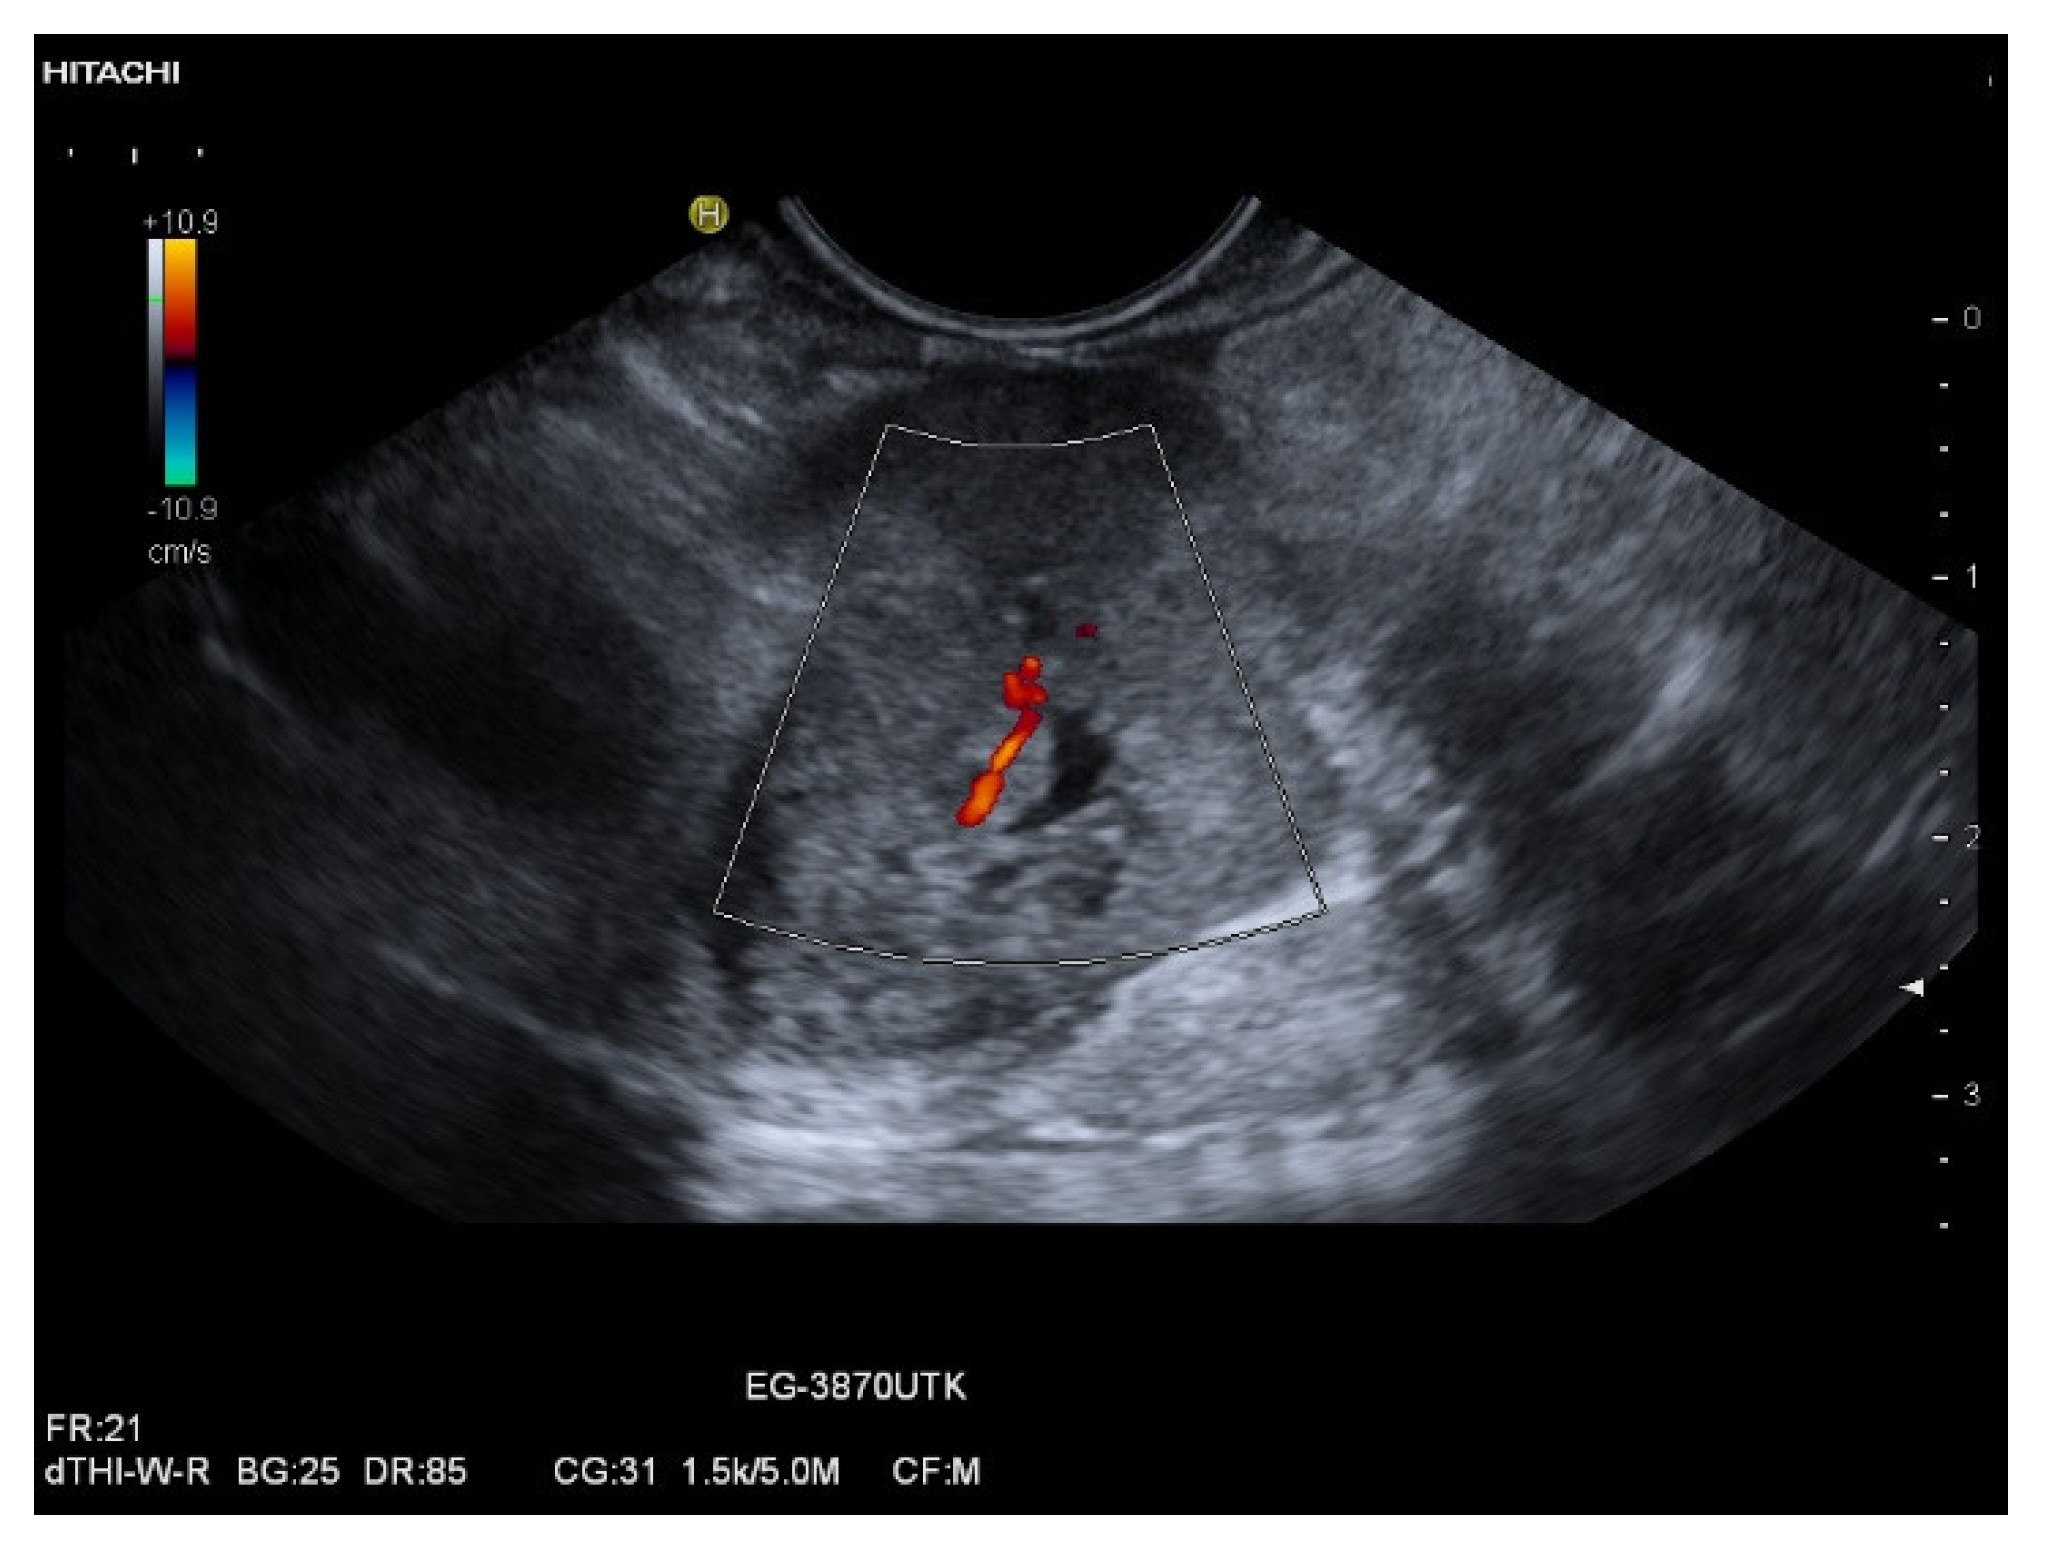

| Colour Doppler Imaging | RCC metastases are hypervascularized Most other pancreatic metastases are hypovascularized | No hypervascularization | Hypervascularized |